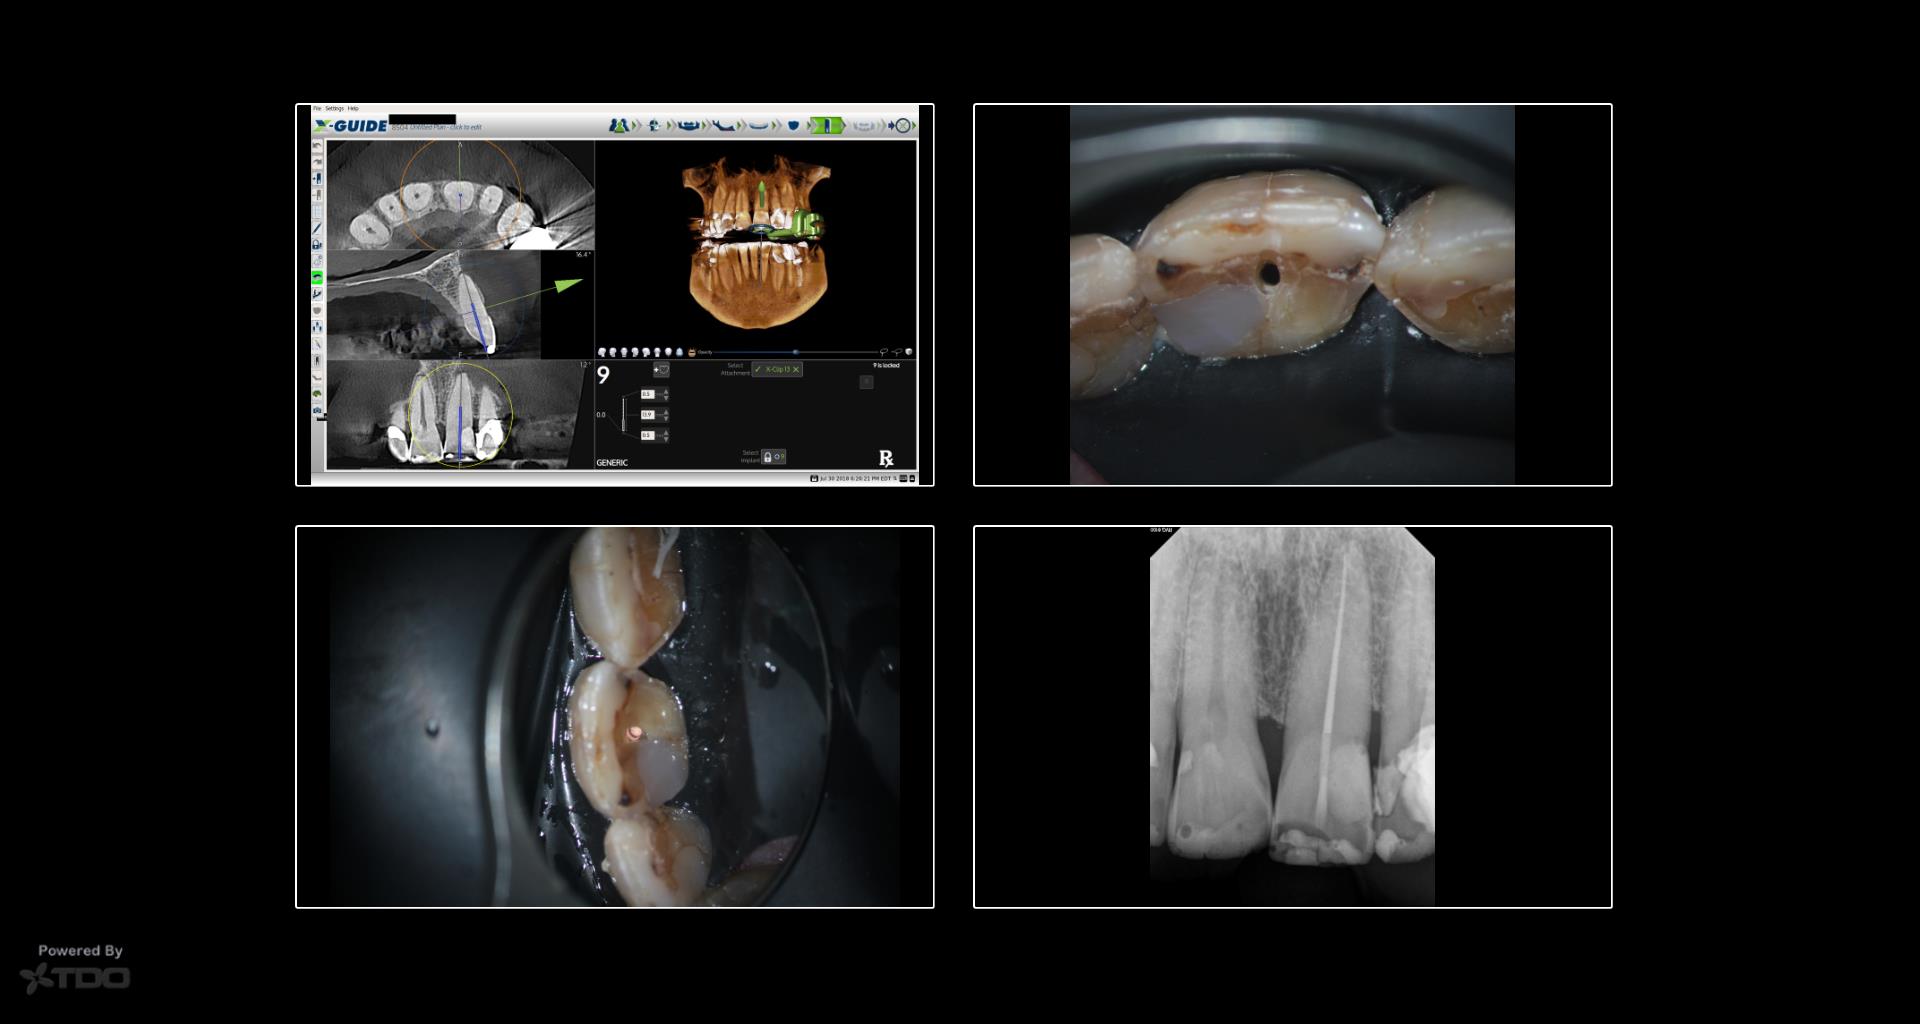

Dynamic navigation has been in dentistry for many years. It remains in its infancy in endodontics but is proving to be very helpful for the access of calcified teeth. This is a case from yesterday in which dynamic navigation was used to allow for a conservative access while locating the calcified canal. -Charles

First off, I think we can both agree that the white line does not tell the story. This was not a one file in and out case. While the largest rotary file used was a 20/04, a 15/02 was used for multiple recapitulations.

For many cases I will utilize the exisiting restoration for the access. Due to the increased difficulty of the access of this case I made the choice to perform the access guided and with the angle to give me the best success to locate the canal conservatively. This goal was accomplished. Furthermore, going through the incisal edge does not go against the preservation of PCD. This is the area of concern.

Impressive demonstration, Charles. Nice utilization of technology. Equally impressive is the lack of voids in such a small space 🙂